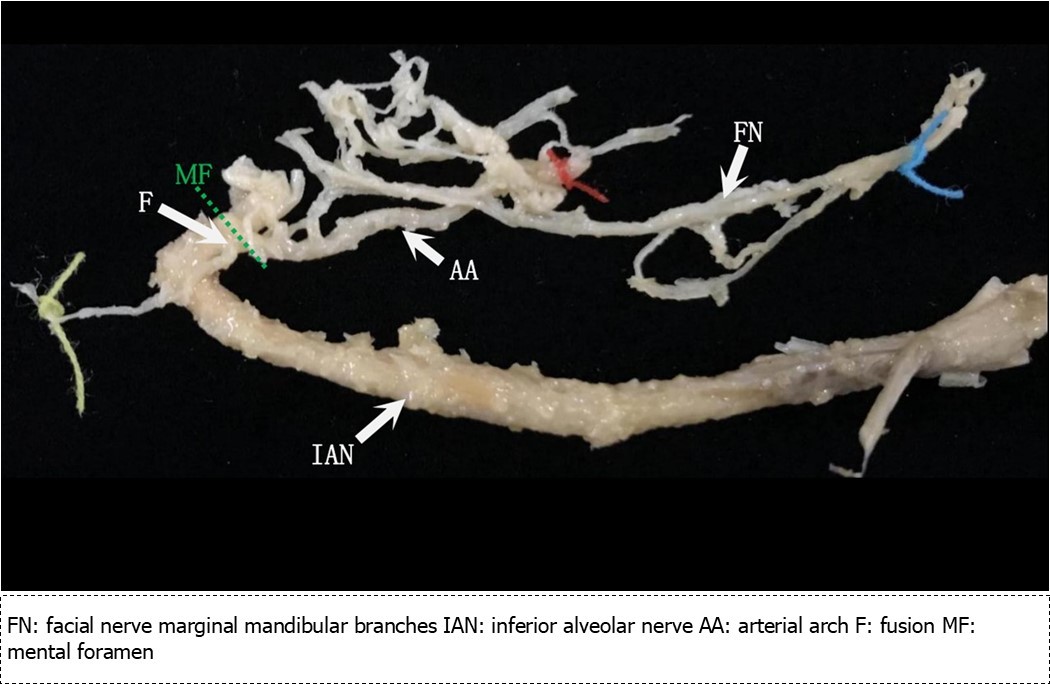

Figure 3.Mental nerve trunk and facial nerve contiguous with the inferior alveolar nerve removed from the mandibular canal

Communication between the inferior alveolar nerve main trunk and the marginal mandibular branch immediately following entrance into the mandibular canal from the mental foramen (Figure 3, F)

From the medial side of the facial nerve, we made thin slices that terminated at the anterior loop. These were used to make histological observations of the communicating branches of the facial nerve and mental nerve. At first, we observed the marginal mandibular branch along with blood vessels and connective tissue. There were several nerves, and there were repeated ruptures, fusions, confluences, and separations at the perineurium level, particularly at the epineurium. Once the inferior alveolar nerve appeared in the section (Figure 4A), we first observed that it was connected at the epineurium (Figure 4C). Next, we observed that the nerve fibers formed a confluence immediately following connection with the perineurium (Figure 4D, E). Following this confluence, there was a complete fusion within the perineurium, as it was impossible to differentiate between the two with hematoxylin and eosin staining. I observed similar findings in all specimens.